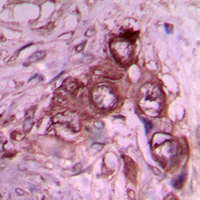

IHC (Immunohiostchemistry)

(Immunohistochemical analysis of Laminin beta 1 staining in human breast cancer formalin fixed paraffin embedded tissue section. The section was pre-treated using heat mediated antigen retrieval with sodium citrate buffer (pH 6.0). The section was then incubated with the antibody at room temperature and detected using an HRP conjugated compact polymer system. DAB was used as the chromogen. The section was then counterstained with haematoxylin and mounted with DPX.)